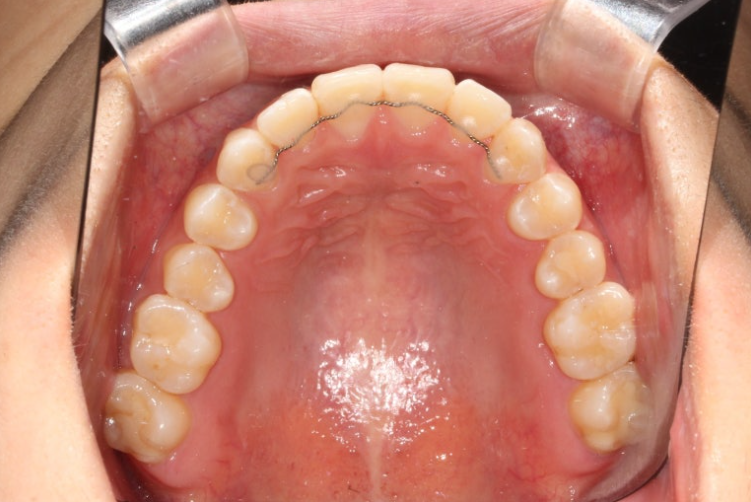

24년 12월에 재교정을 위해 내원하신 분 입니다.

중학교때 교정을 했으나 철사유지장치가 떨어지면서 앞니가 다시 틀어진 상태입니다.

앞니 높낮이 단차와 개방교합도 보입니다.

24.12